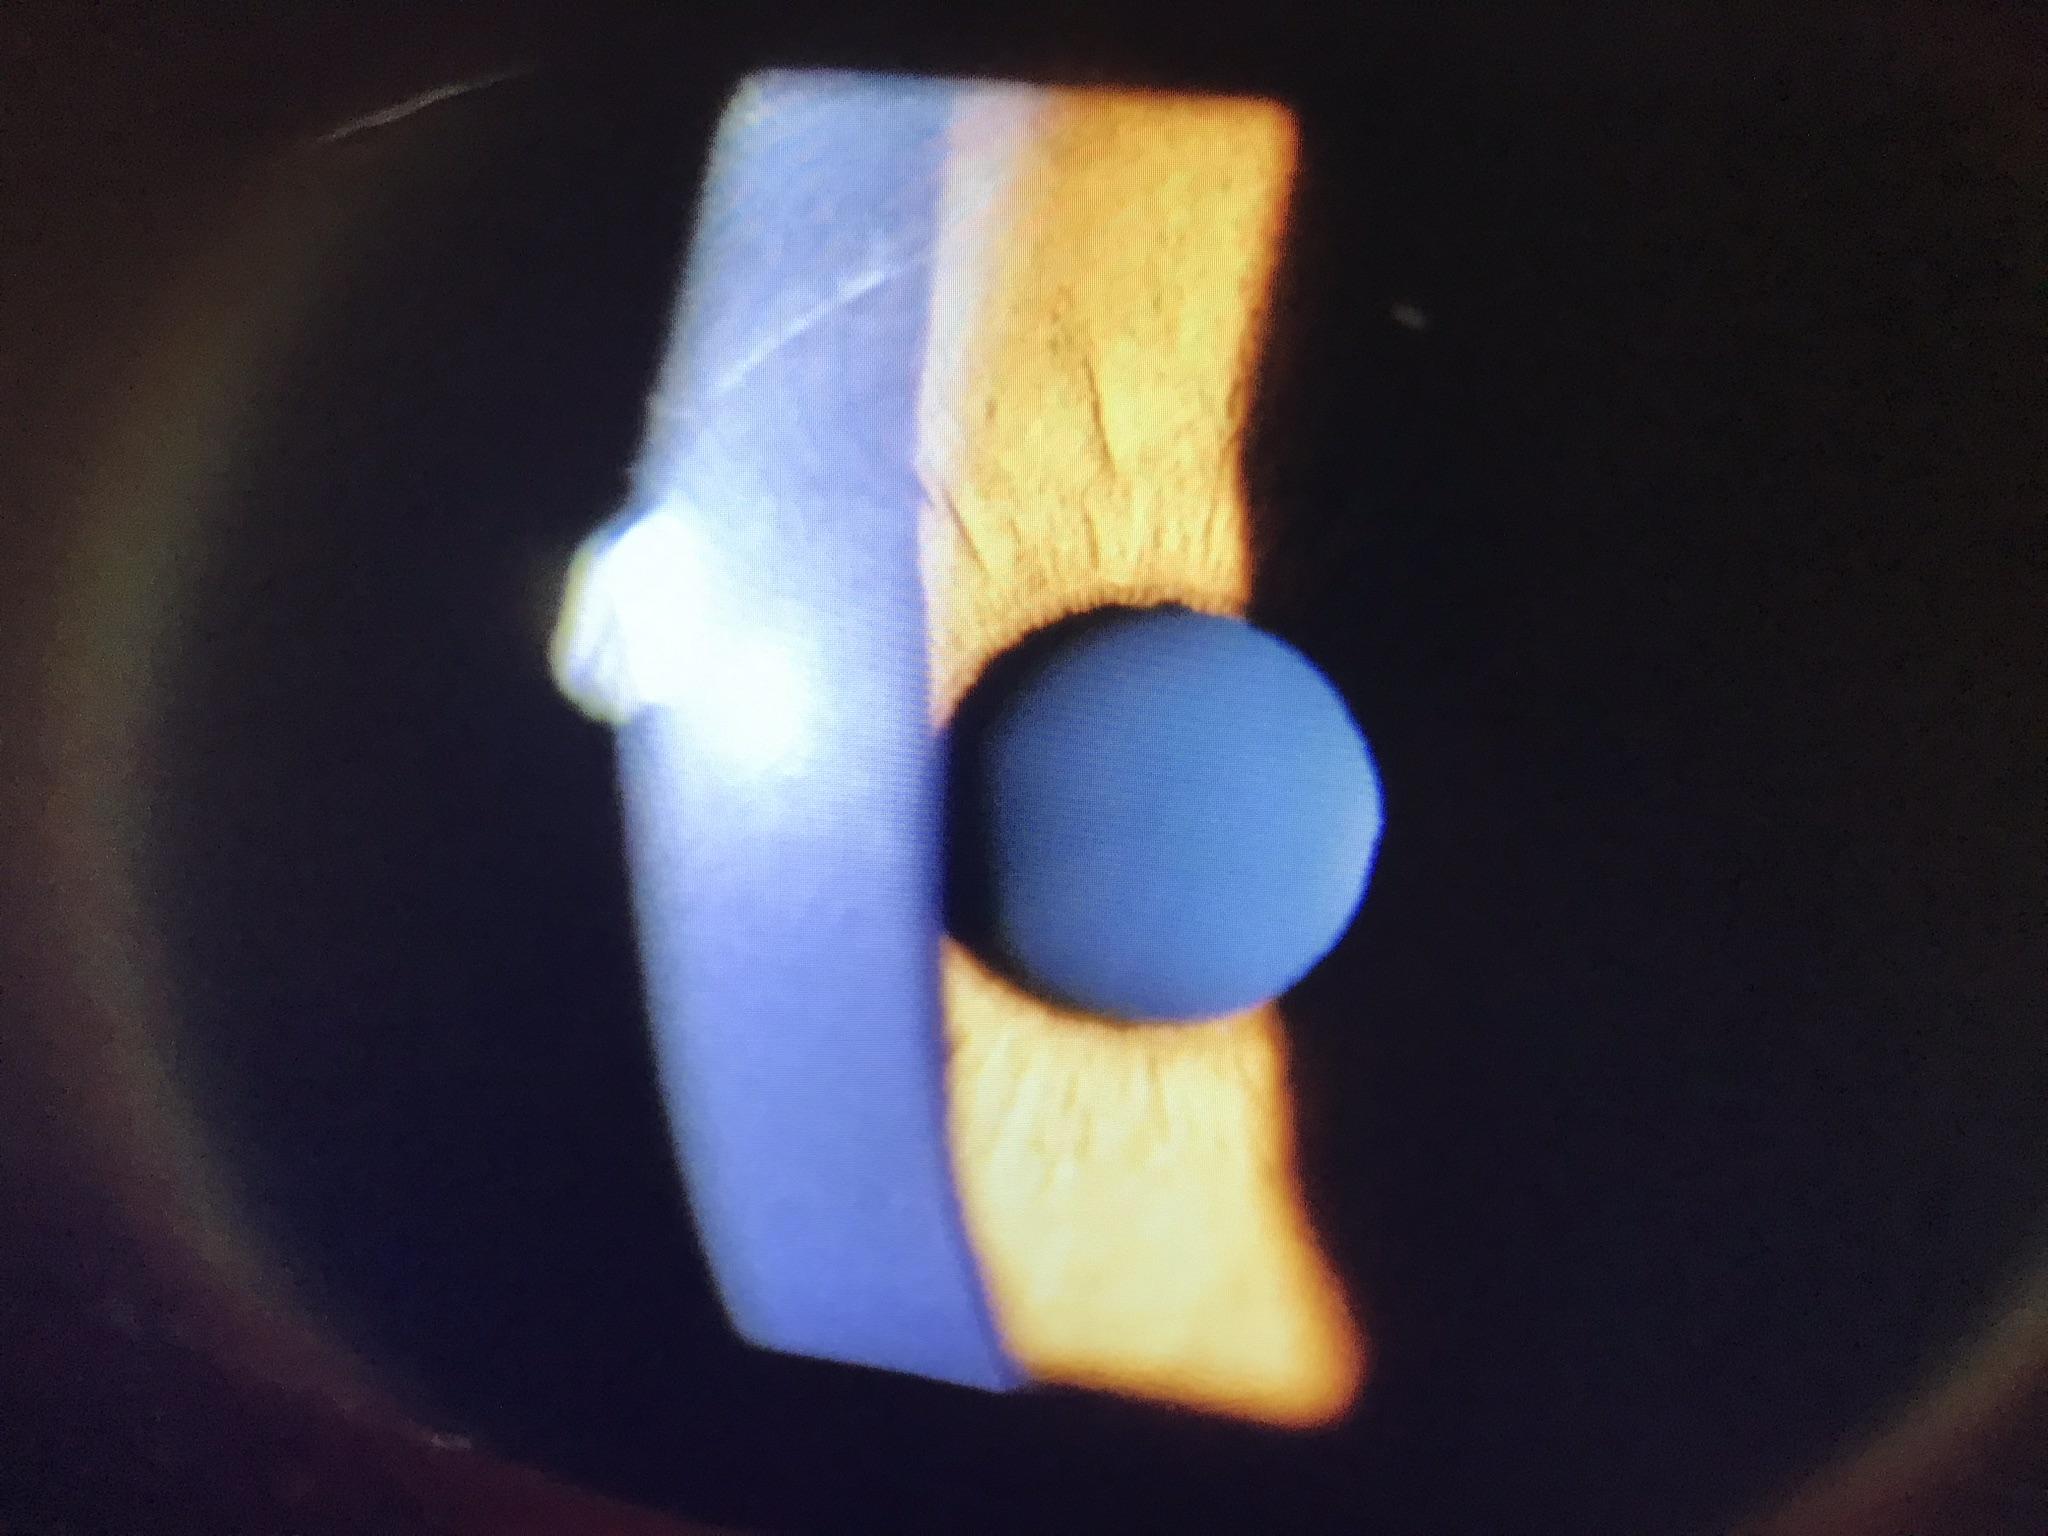

植入式隱形眼鏡手術(ICL)的鏡片模型。

ICL屬於「眼內」手術,醫生會在患者眼球角膜側切開約4毫米,先加入專用啫喱穩定眼前房,再放入捲起的「鏡片」於眼球虹膜與晶體間。採用可摺疊的「鏡片」使手術切口更細,甚至可不用縫針,而「鏡片」位置會因應患者的散光緯度調整,待吸走先前置入的啫喱後手術即完成。